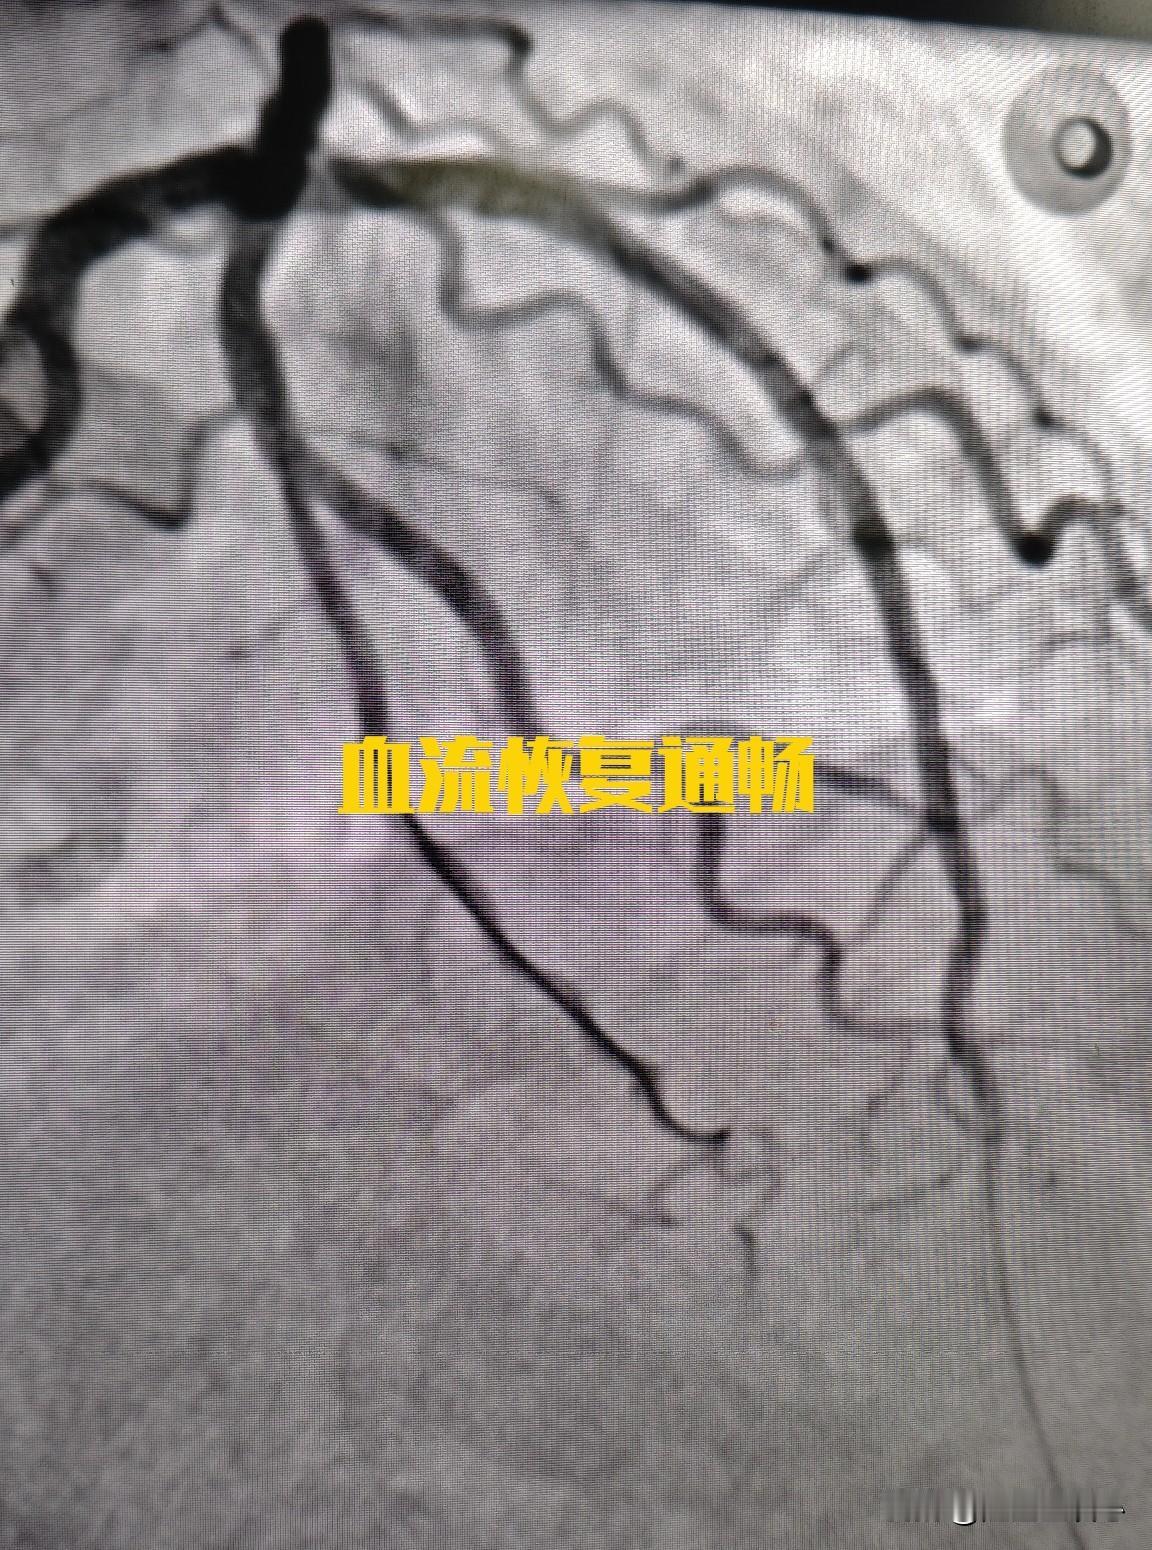

来看看心脏血管斑块破裂是什么样子的。一个 75 岁的男性患者,在医院就诊时,突发心脏骤停倒地,经胸外按压积极抢救后恢复意识。 紧急做了冠状动脉造影,发现是前降支中段一个不稳定斑块出现的破裂,局部有血栓形成。这就是导致患者突发意识丧失的原因。导丝通过前降支病变后,植入支架三枚,把斑块附近的有动脉硬化的血管全部覆盖,血流恢复通畅。 其实这里的狭窄本身并不严重,狭窄程度大约在 70% 左右。突然出现急性心肌梗塞,并不是说堵塞非常严重,而是一些不稳定的斑块突然破裂,导致的局部血栓形成,进而堵塞整个血管。 冠心病的治疗,一方面是预防血栓,另外一方面是尽量稳定动脉硬化斑块,让其不容易破裂。稳定斑块的方法,最主要的是降低低密度脂蛋白胆固醇,一旦发现有冠心病,最好把低密度脂蛋白胆固醇降低到 1.8 以下,最好降低到 1.4 以下。这样斑块才会更加稳定,不容易破裂,也就不容易突发急性心肌梗塞了。